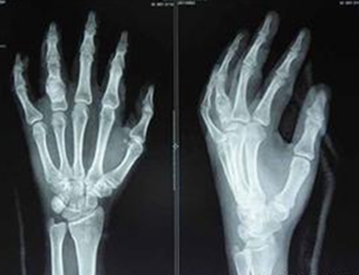

(图:周老师手部CT图)

HD-热层析检测:腕关节炎性介质明显,且有加重、增多趋势,腕关节痛重,累及关节往肘关节发展。

检查数据:抗链球菌溶血素O(ASO) 284.8 u/ml,类风湿因子O(RF) 16.35 IU/ml,血沉(ESR) 31.6 mm/h。

抗链球菌溶血素O(ASO) 35.7 u/ml;类风湿因子O(RF) 6.15 IU/ml;血沉(ESR) 6.38 mm/h。